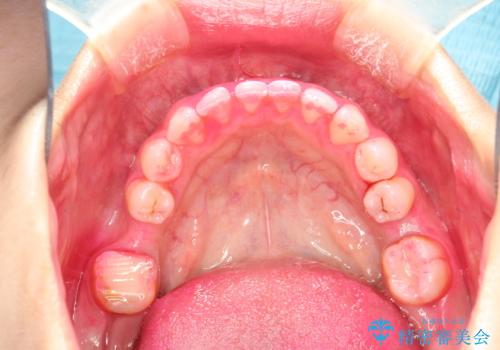

開始前

かなり久しぶりの歯科医院との事で、全体的に古くからの歯垢・歯石が多く付着していたため、自費クリーニング(PMTC)60分コース・歯周ポケット検査(保険適応)を行いました。